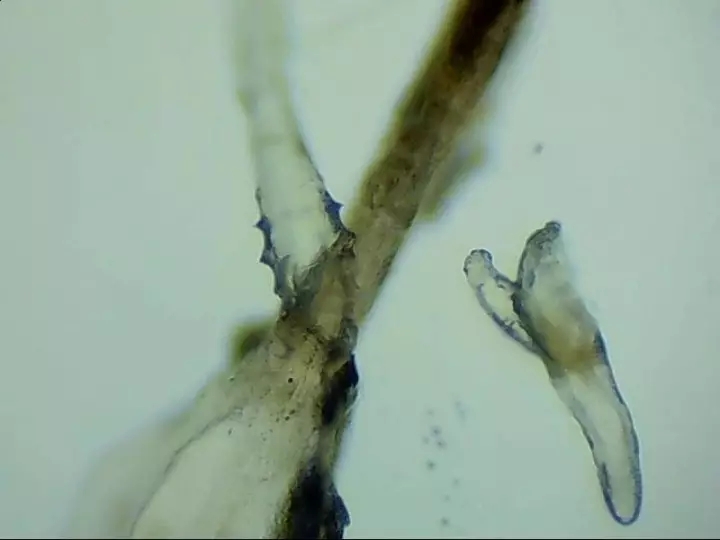

寄生在人體的蠕形螨以毛囊蠕形螨為主,皮脂蠕形螨次之。在眼部,毛囊蠕形螨寄生于睫毛毛囊,而皮脂蠕形螨則分布于睫毛毛囊的皮脂腺和瞼板腺內(nèi)。兩種螨蟲(chóng)經(jīng)常生活在睫毛和眉毛根部,它們通過(guò)生產(chǎn)的卵、排泄的廢物和分泌的分泌物導(dǎo)致過(guò)敏反應(yīng),并在人體免疫系統(tǒng)變?nèi)鯐r(shí)引起眼部感染。

蠕形螨性瞼緣炎門(mén)診配備有光學(xué)顯微鏡鏡檢、活體激光共聚焦顯微鏡檢查等高新設(shè)備可作出精準(zhǔn)診斷。并有多種治療手段全方面驅(qū)逐、殺死螨蟲(chóng)。